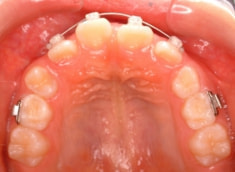

治療開始から約10ヶ月後

治療法:上顎拡大装置+フルパッシブブラケット(クリアスナップ)+フェイスマスク等

治療期間:1年3ヶ月

治療分析:日本人の反対咬合や下顎前突は、上顎の劣成長を伴なうことが多いので、上顎を側方拡大と前方に牽引しました。側方拡大方法は急速拡大で、正中口蓋縫合の拡大を行い、横口蓋縫合を剥がす効果で、前方牽引の効果を促進します。